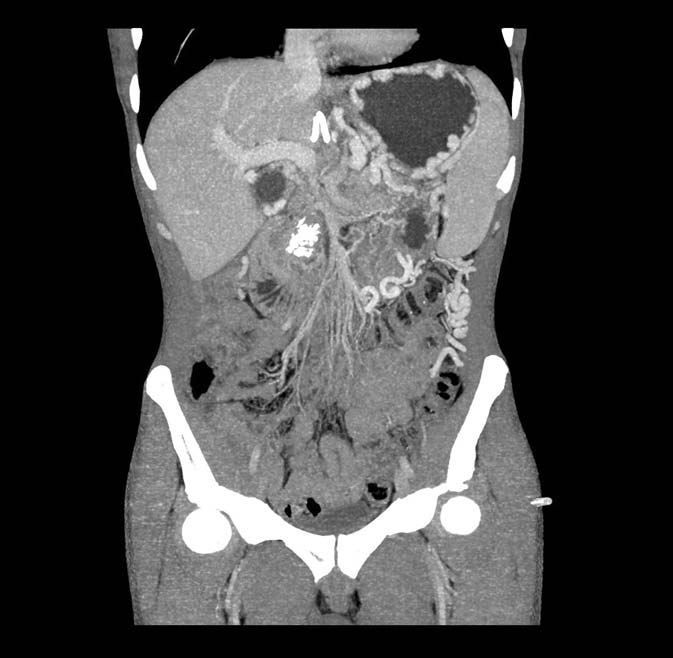

Мультиспиральная компьютерная томография органов брюшной полости и забрюшинного пространства: «Псевдотуморозный калькулёзный хронический панкреатит. Постнекротические псевдокисты головки поджелудочной железы. Забрюшинно-панкреатический трубчатый свищ. Признаки флеботромбоза верхней брыжеечной и селезёночной вен, признаки портальной гипертензии, многочисленные портокавальные анастомозы» (рис. 1, 2).

Рис. 1. Компьютерная томограмма органов брюшной полости

Рис. 2. 3D-реконструкция портальной каверномы по данным компьютерной томографии